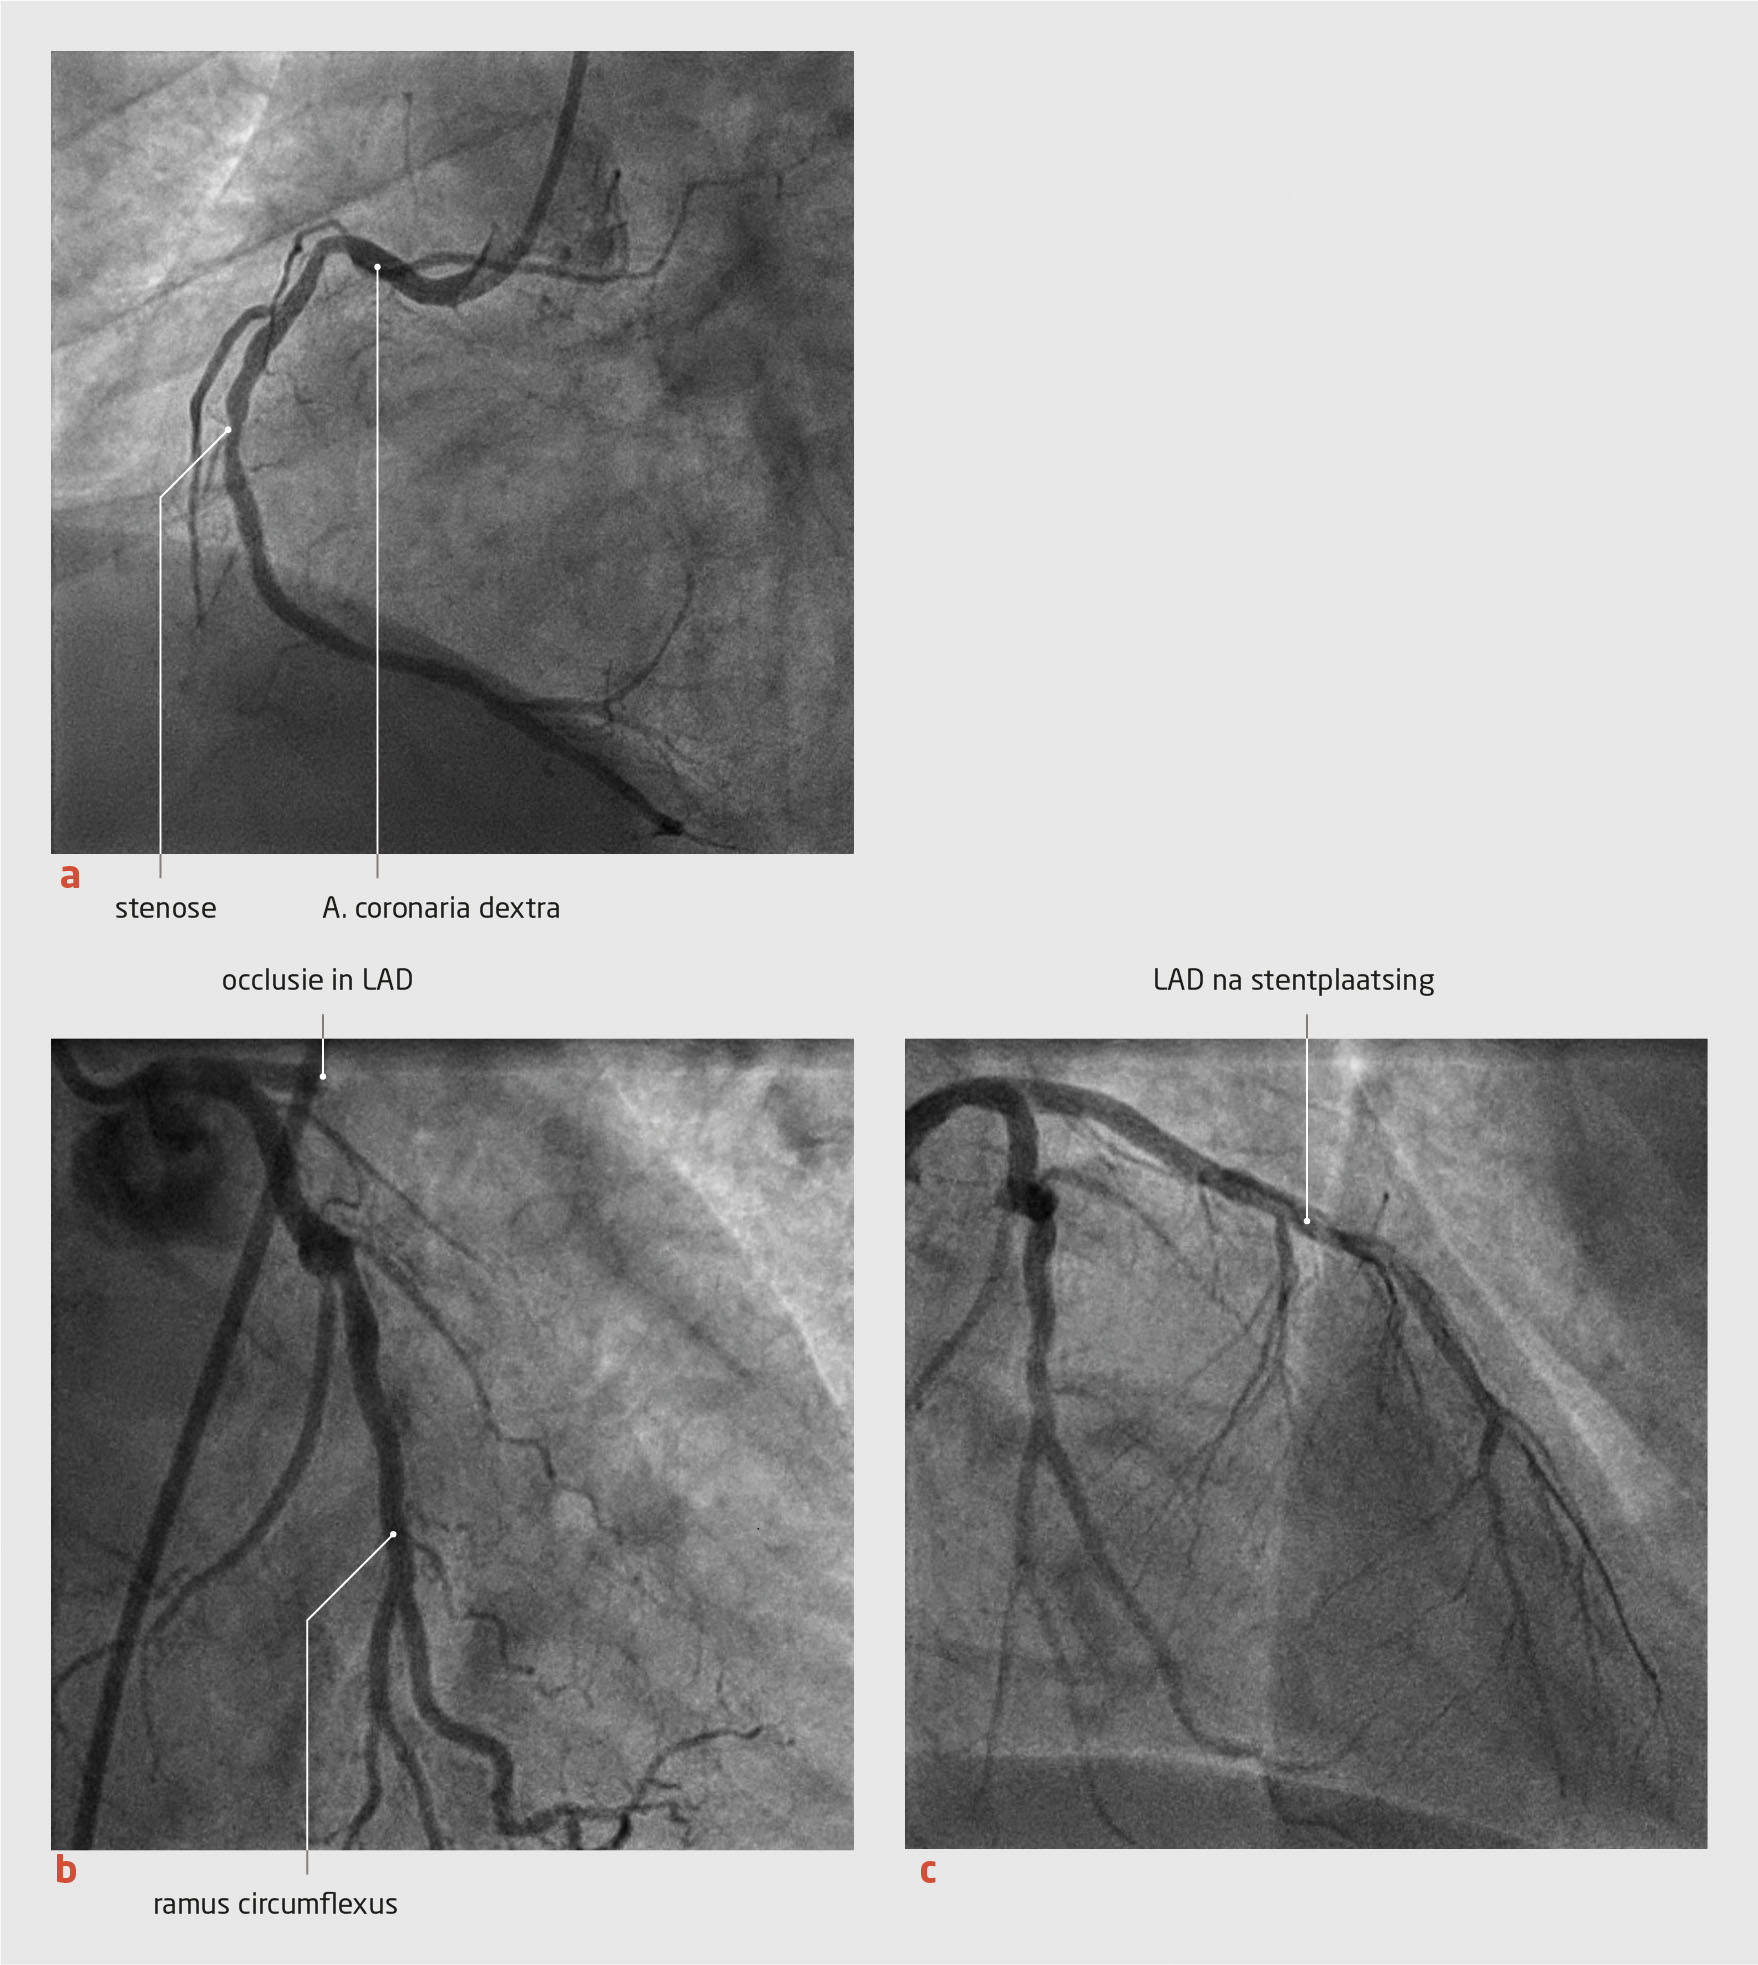

Casus

Een 63-jarige man kreeg postoperatief een anafylactische reactie op een intraveneuze gift diclofenac. Tijdens de behandeling van de anafylaxie trad myocardischemie op, achtereenvolgens veroorzaakt door een spasme van de rechter coronairarterie en een occlusie van de ramus interventricularis anterior (‘left anterior descending artery’) van de linker coronairarterie. Ondanks een percutane coronaire interventie trad infarcering van de voorwand op. Een verminderde linkerventrikelfunctie resteerde.